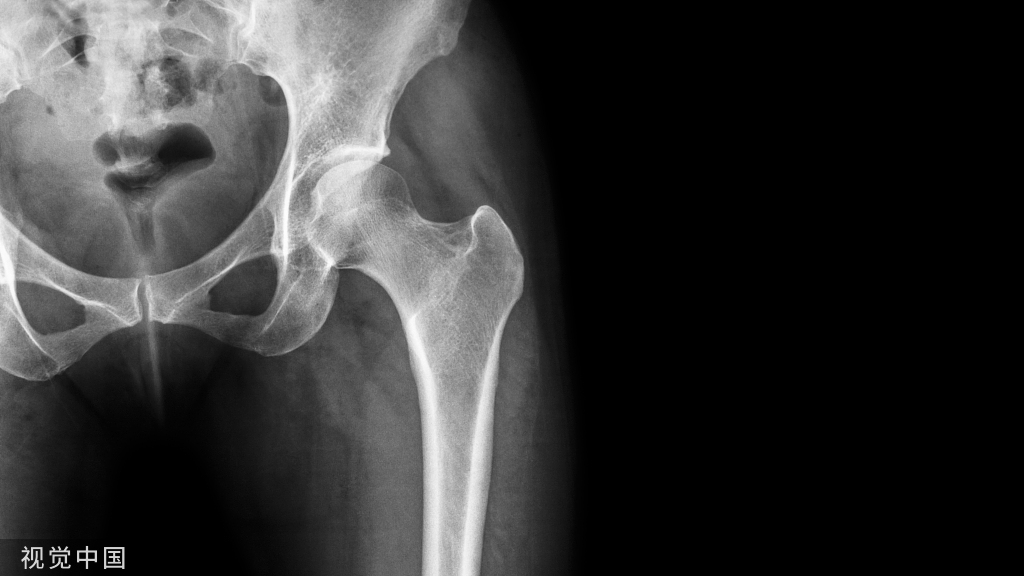

上述两个病例更是通过截断腓骨实现了胫骨骨折的愈合反思 腓骨不该固定?疑问 腓骨要不要固定?